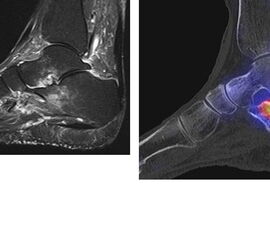

Abbildung 8.1. a bis f.: Patient mit Z. n. OSG-Distorsion vor 8 Monaten und konservativer Therapie. Anhaltende Schmerzen im Bereich des linken Innenknöchels. Im MRT bestand der Verdacht auf eine symptomatische kleine osteochondrale Läsion im medialen linken Talus (Abbildung 8.1. a und c). Zur weiteren Klärung erfolgte eine SPECT/CT 30 Tage später, welche jedoch im Gegensatz zur MRT eine fokale Mehrspeicherung an der tibialen Insertion des Deltabandes nachwies. Die Tatsache, dass die SPECT/CT spezifischer als die MRT symptomatische Bandläsionen detektieren kann wird untenstehend ausführlich thematisiert.

Abbildung 8.2. zeigt den Fall eines Patienten mit Verdacht auf ein knöchernes posteriores Impingement. Es bestanden Beschwerden dorsal bei Plantarflexion und ein Z. n. Distorsion des linken OSG vor 2,5 Jahren. Im MRT 2 Monate vor der SPECT/CT keine wegweisenden Befunde. Im SPECT/CT eindeutige fokal deutliche Mehrspeicherung im Bereich des Processus posterior tali.

Abbildung 8.3.a bis d demonstrieren Bilder einer Patientin mit Z. n. Arthrodese des linken OSG vor 6 Jahren. Das MRT ist bei ausgedehnten Metallartefakten nur bedingt aussagekräftig und weist nicht auf die auffälligen Befunde im SPECT/CT hin. Es bestehen sowohl fokale Stressreaktionen im Bereich eines Os trigonum und lateral im USG.

Abbildung 8.4.a bis d: Bilder einer Patientin mit chronischen Schmerzen im lateralen unteren Sprunggelenk links. Im MRT V. a. akzessorisches Knochenelement. Anamnestisch Beschwerden im Bereich des linken Sprunggelenkes seit 5 Monaten. Zuvor intensive sportliche Betätigung. Unter anderem tägliche atypische Belastung beider Füße durch Hinknien im Rahmen der Tätigkeit als Erzieherin. Diese Patientin hat nebenbefundlich bilaterale Akzessoria bzw. einen beiderseits angelegten Talus secundarius, der linksseitig jedoch nicht für die Symptomatik verantwortlich ist (die Bilder davon werden in Abbildung 3.5. gezeigt). Verantwortlich für die Symptomatik ist ein links posterolateral am Talus atypisches Knochenelement in einer Mulde mit engem Bezug zum unteren Sprunggelenk, DD atypisches laterales Os trigonum oder DD atypische Osteochondrosis dissecans. Die MRT konnte nicht differenzieren, wo die Schmerzursache genau lag. Im SPECT/CT (Abbildung 8.4.b und d) eindeutig fokale Mehrspeicherung im Bereich des atypischen Knochenelementes. Intraoperativ bestand der Aspekt einer Osteochondrosis dissecans.